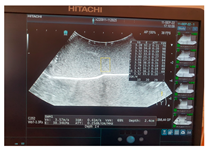

| Ultrasound | ![]() | ![]() | ![]() |